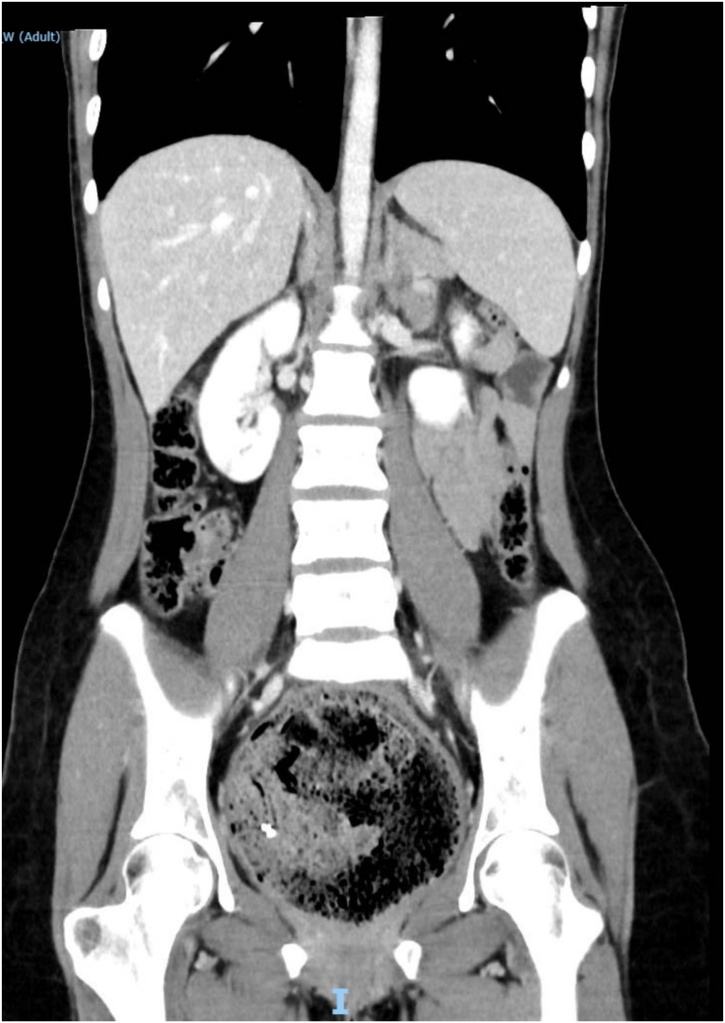

A 19-year-old Caucasian female patient was referred to General Surgery Department after her PCP found megacolon and megarectum in a computed tomography (CT) scan of the abdomen and pelvis (Fig. 1, Fig. 2, Fig. 3). Her evaluation and diagnostic procedures were performed by a board-certified general surgeon with colorectal surgery training. She had a lifelong history of intermittent abdominal pain as well as constipation requiring daily laxatives and enemas. Other than that, she did not have a history of medical or surgical problems. She did not smoke and her family history was unknown since she was raised by her aunt. Her abdominal exam was within normal limits. Her ano-rectal exam was normal on inspection, the digital rectal exam demonstrated a normal resting tone as well as hard stool in the rectal vault. The CT scan was significant for a severely distended sigmoid colon and rectum. Her lab work included a complete blood count and a comprehensive metabolic panel, these were within normal limits. Given her presentation the work up included: colonic transit study (Fig. 4), barium enema (Fig. 5) and a full thickness rectal biopsy after rectal de-impaction. Anal manometry was not performed. The colonic transit study (Sitz Marker Test) displayed most of the markers in her sigmoid colon and rectum at day number five. The Barium enema showed similar findings to those of the CT scan which included a dilated rectum starting immediately above the anorectal ring. She was taken to the operating room for a rectal biopsy. Under general anaesthesia and in lithotomy position a manual de-impaction was performed followed by rectal irrigation and a full thickness rectal biopsy. An anoscope was used to identify the level of the target area. In order to include the submucosa 2 full thickness rectal biopsies at 1.5 and 3 cm from dentate line in the posterior aspect were taken. Distal and proximal to this location a 2-0 Vicryl full thickness traction stitch was placed. This allowed total control of the tissue to ensure full thickness specimens. Both defects were closed with running 2-0 Vicryl. The patient tolerated the procedure well; she was discharged home the same day on a soft diet and had no post-operative complications. Pathology results showed the lack of ganglion cells in the submucosa (Fig. 6a-b). Routine H&E staining, as well as Immunohistochemistry stains for S100, Smooth Muscle Actin (SMA) and Calretinin were performed. Both SMA and Calretinin were negative despite appropriate controls which confirmed diagnosis of Hirschsprung’s disease (Fig. 7a-b). The patient was then referred to a tertiary care center. The chief of Pediatric Surgery took over her case. She underwent manual fecal de-impaction, a confirmatory rectal biopsy, laparoscopic seromuscular sigmoid biopsies for levelling and a diverting loop ileostomy for decompression of the dilated colon and rectum. The distal sigmoid colon biopsy showed few ganglion cells; the proximal colon had a normal amount. Seven months later she underwent an uneventful laparoscopic proctectomy with perianal colo-anal pull through procedure of which she recovered well. The operation was uneventful. Two months later her loop ileostomy was closed. She has been doing well. She is having two bowel movements a day with very good control and no longer suffers from constipation.

Fig. 1.

CT scan showing megarectum and fecaloma in a coronal section.